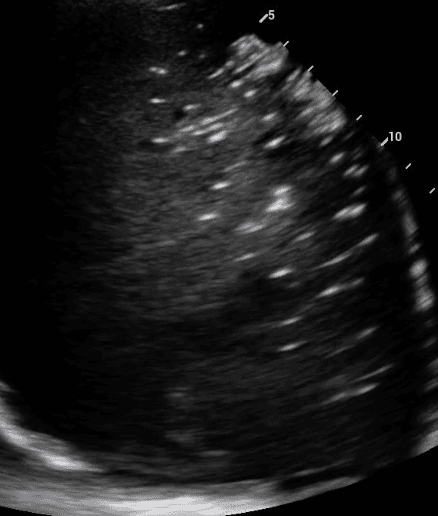

Lung ultrasound will also demonstrate diseased lungs that are filled with fluid or cellular debris. Lung consolidations often have bright air bronchograms, which represent air trapped in fluid filled bronchi.